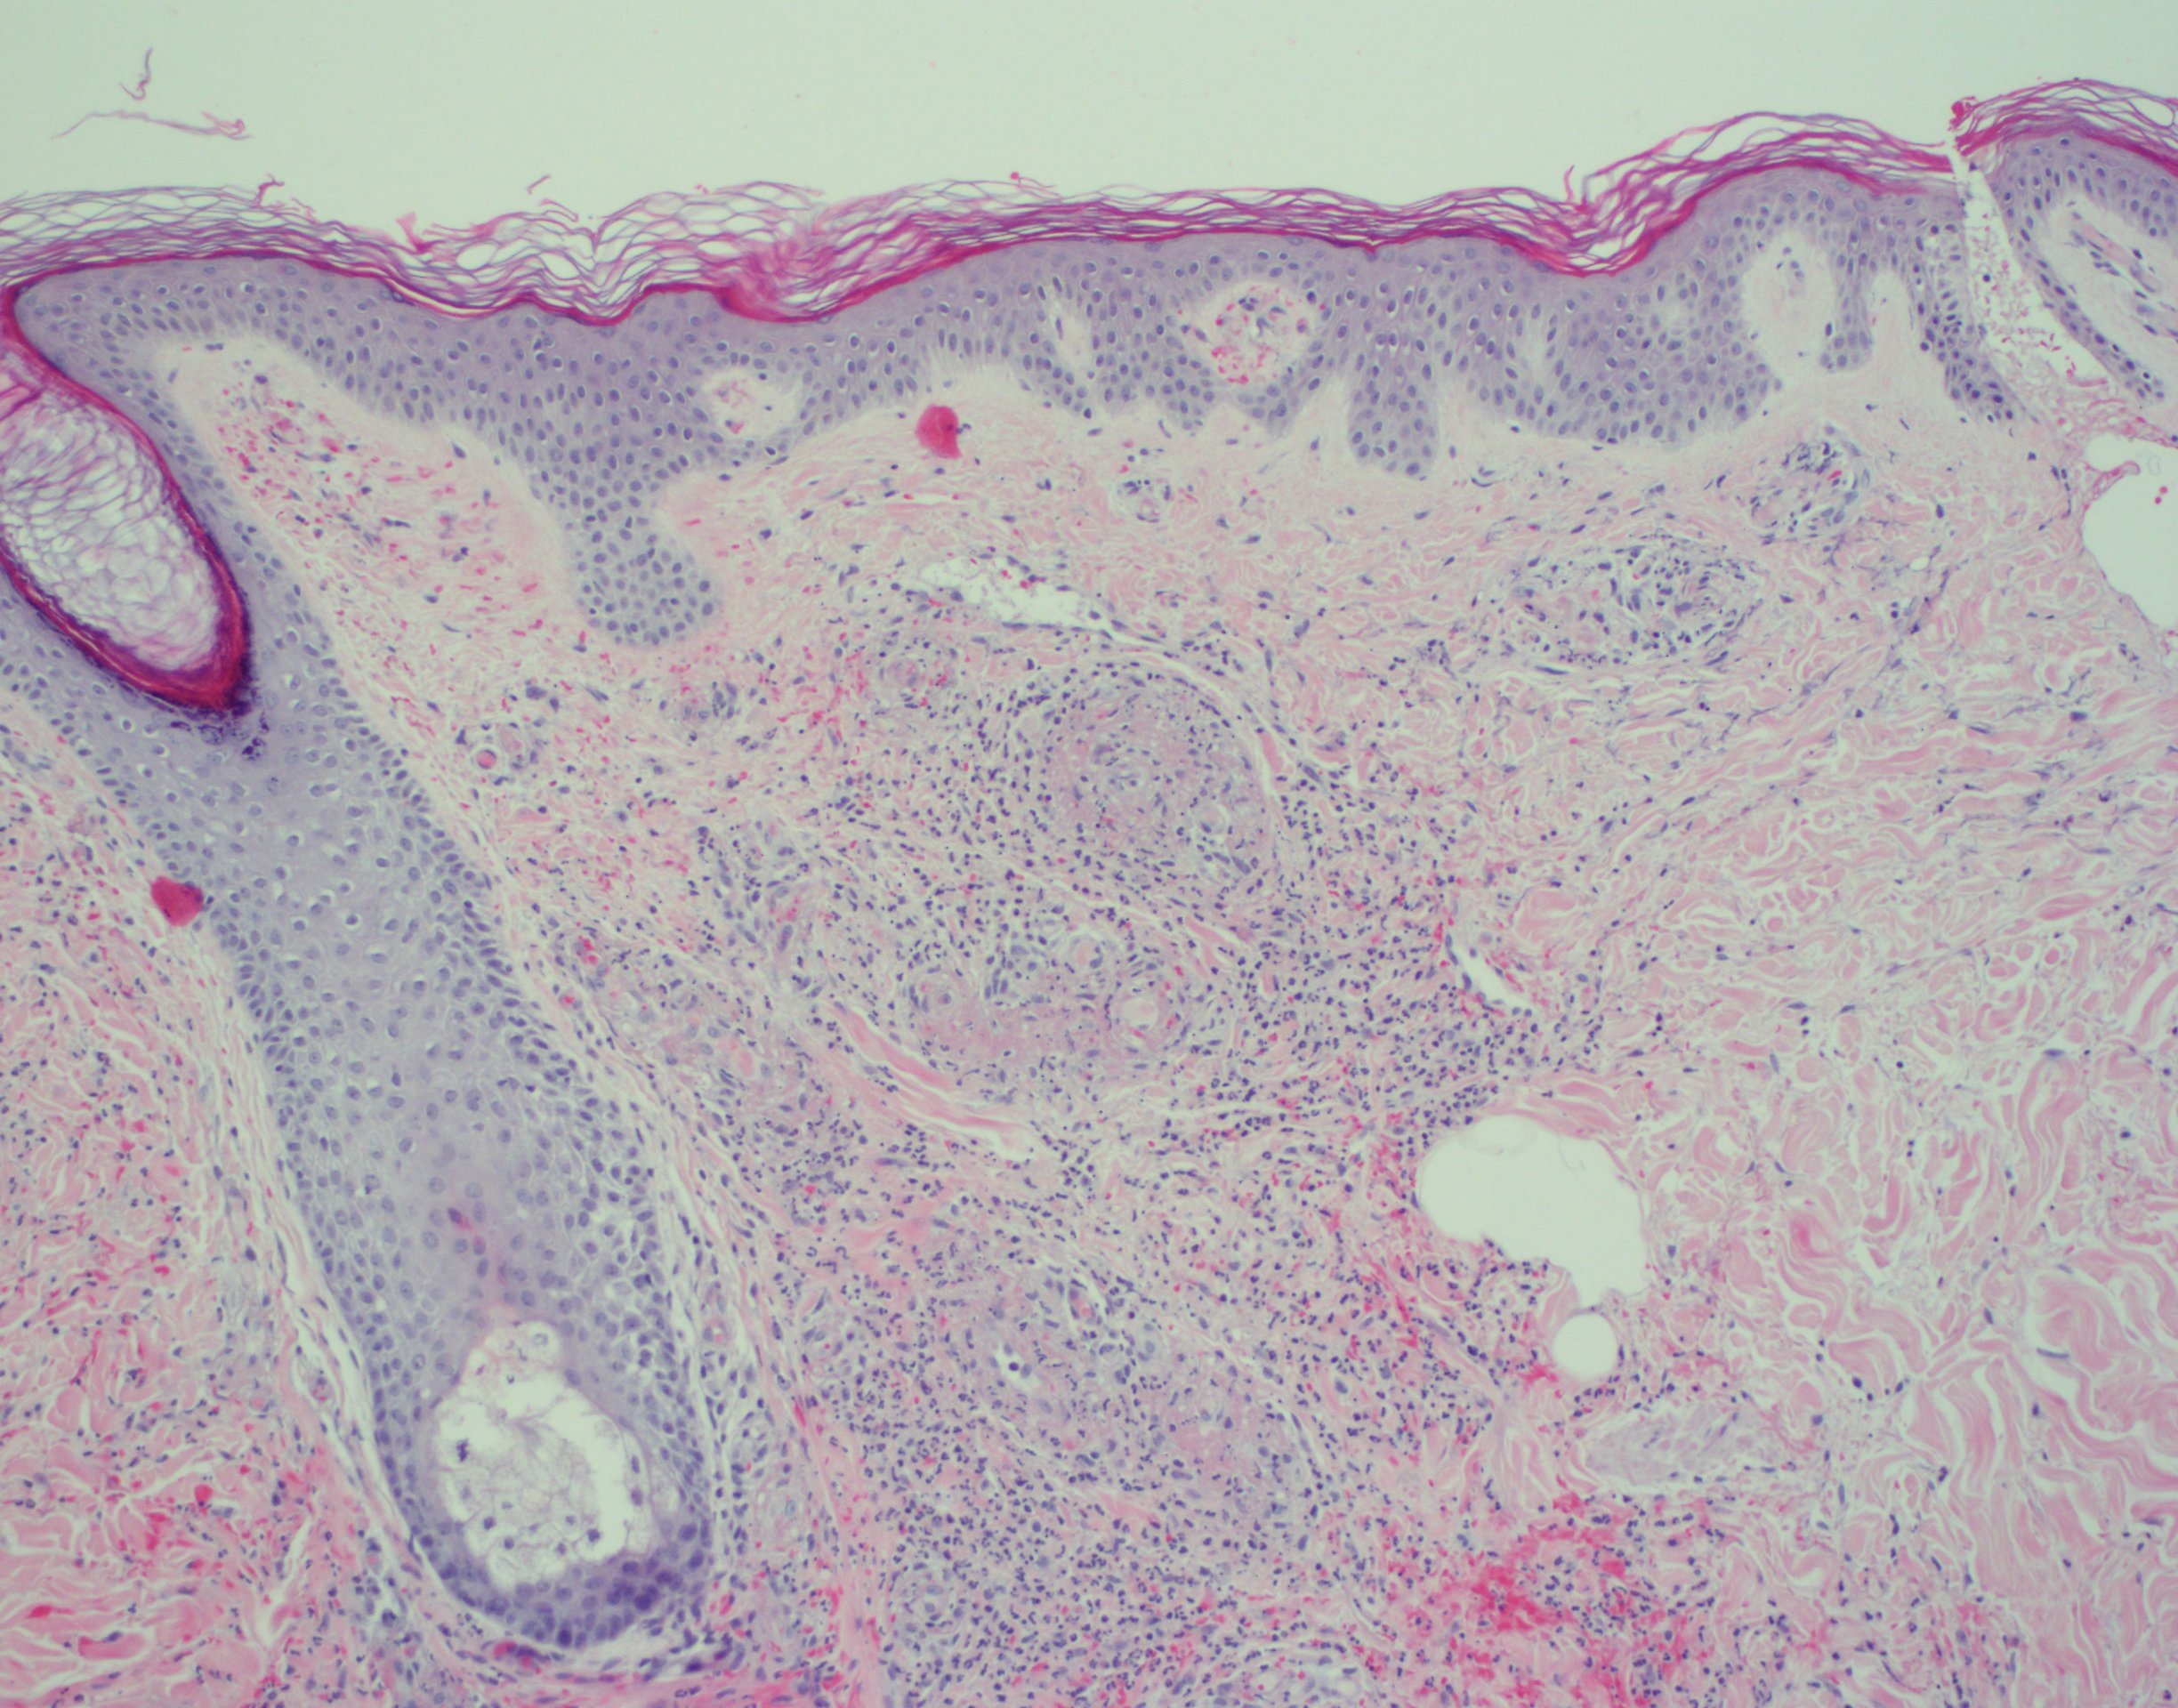

The rapid development of coalescing palpable purpura, acute kidney injury, and joint arthralgias subsequent to initiating a new medication strongly suggests a hypersensitivity vasculitis.1 Histopathologic study revealed neutrophilic vasculitis with red blood cell extravasation, perivascular and interstitial neutrophils, nuclear dust, and vascular damage with fibrin deposition (Figures 2-4). Under direct immunofluorescence, deposition of immunoglobulin G, immunoglobulin A, C3, immunoglobulin M, and fibrin were observed in the blood vessels and vessel walls. These findings confirmed the diagnosis of LCV.2

Figure 3. Section from a punch biopsy of skin lesions demonstrating neutrophilic vasculitis with erythrocyte extravasation, perivascular and interstitial neutrophils, nuclear dust, and vascular damage with fibrin deposition (hematoxylin-eosin; ×100 magnification)